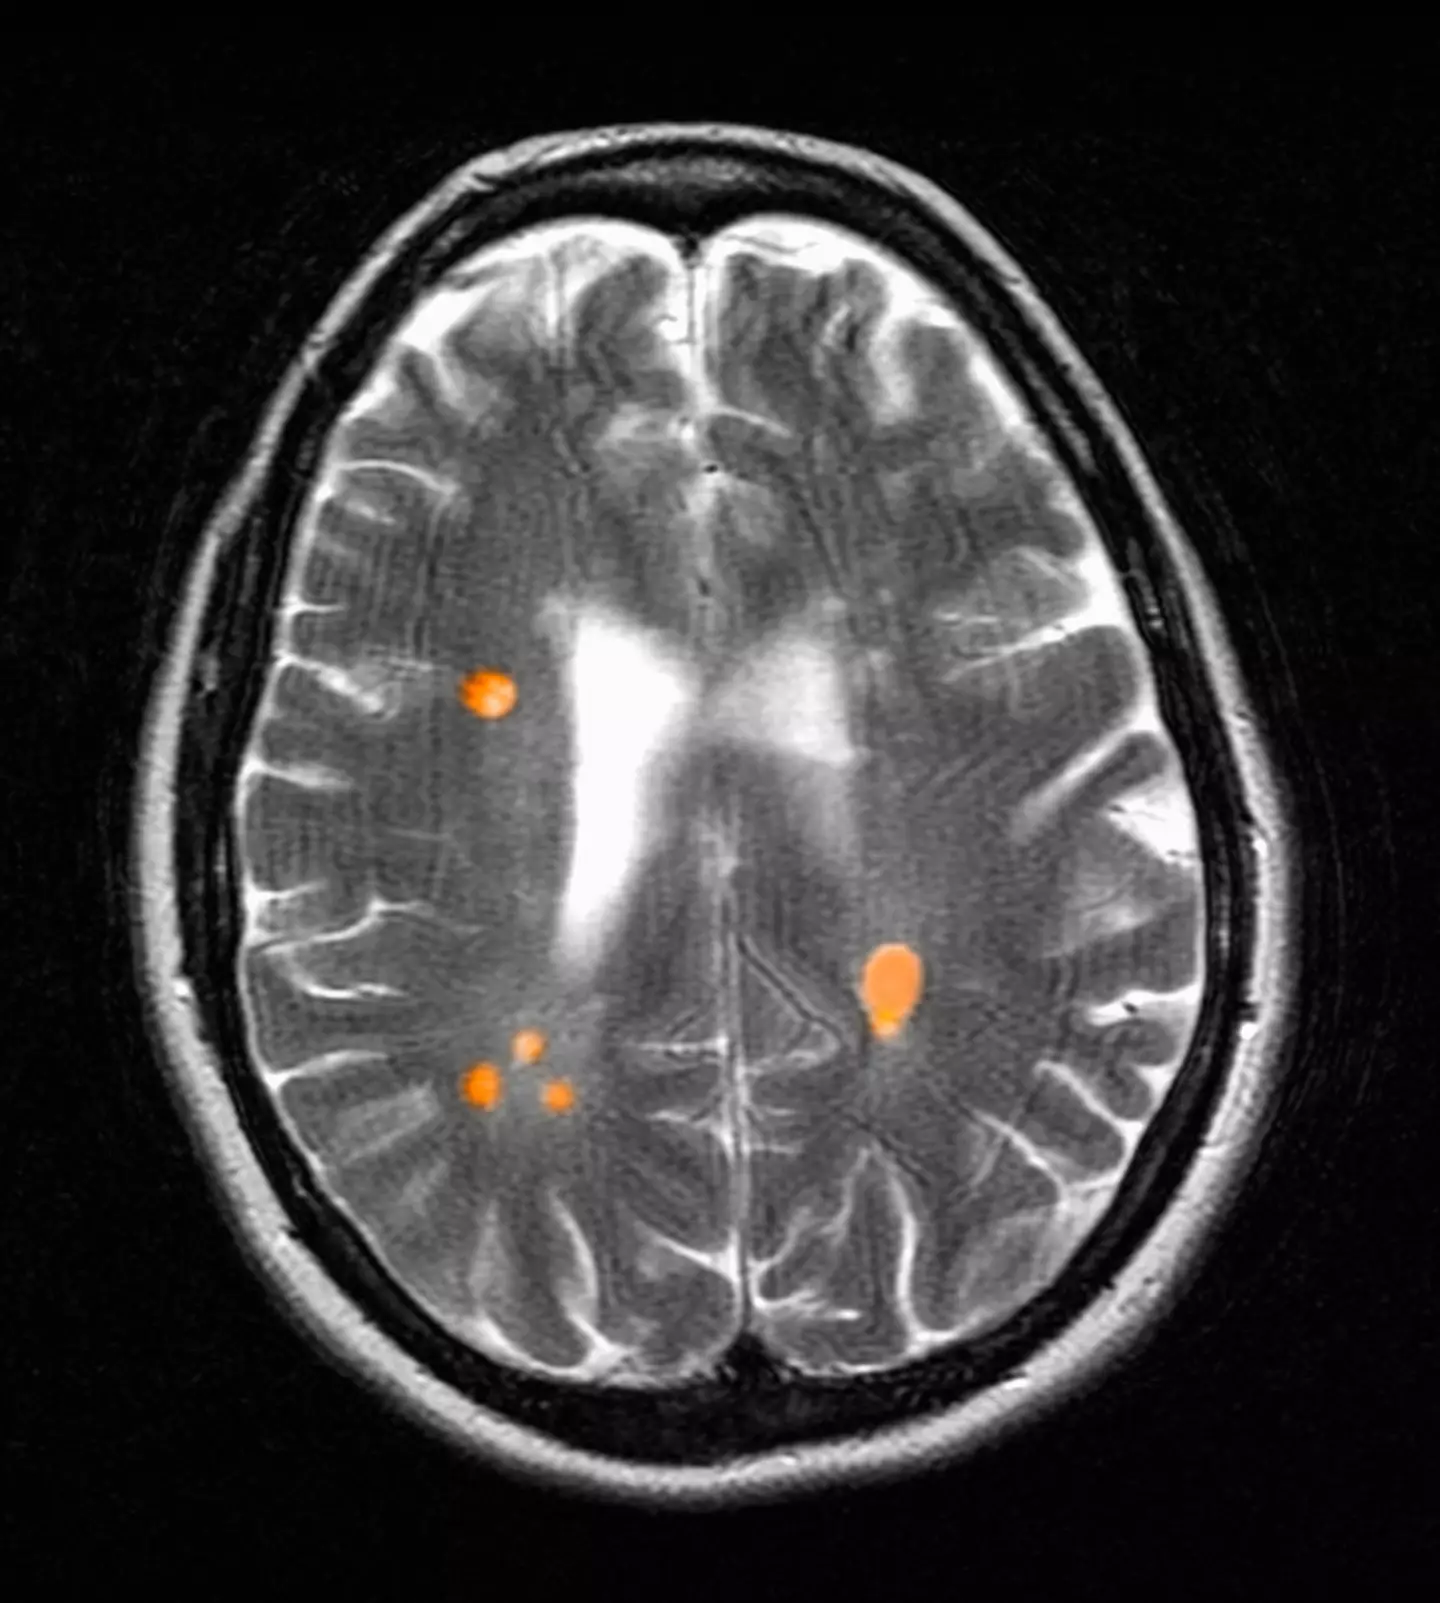

The actress was then sent for an MRI scan to check out what the cause could be.